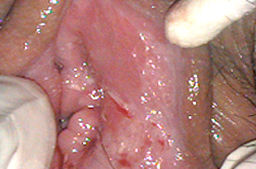

Desde hace muchos años se ha observado que si la piel infectada por Virus del Papiloma Humano (piel con lesiones o infectada) es destruida, se regenera con piel sana y el paciente puede eliminar la infección con una tasa de éxito variable dependiendo del tipo de aparato usado, y de la mejora que se obtenga en el sistema inmunológico de cada paciente.

Se han utilizado el electrocauterio y el asa diatérmica para la electrocauterización de las lesiones con una tasa real de éxito muy regular pues existe curación en el 93% de los pacientes, pero el 24% vuelven a presentar las lesiones en menos de 2 años, por lo que la tasa real de éxito es del 69%, y además tienen el inconveniente de ser muy dolorosos ya que no existe un control preciso de la profundidad con la que se destruye la piel por lo que penetran más de 1 mm, y afecta las terminaciones nerviosas, debido a esto los pacientes presentan dolor en los genitales externos, (las mujeres en vulva y los varones en pene) cuando practican deportes que ocasionan fricción en la zona o cuando tienen relaciones sexuales y esto puede durar hasta varios meses. Debido a las secuelas actualmente no se recomiendan dichos procedimientos para tratar los siguientes órganos: vagina, vulva, periné, región peri anal, ano y pene, con lesiones extensas.

La Crioterapia o Criocirugía ha sido utilizada para destrucción de la piel con lesiones del Virus del papiloma humano. Tiene el mismo inconveniente que los aparatos de electrocirugía ya que no mide la profundidad adecuadamente. La tasa de éxito inicial es del 83% con una recurrencia del 28% los primeros dos años. Debido al daño de las terminaciones nerviosas puede ocasionar, hipersensibilidad en los genitales.

Para destruir la piel también se ha utilizado el ácido triclorácetico ya que los dermatólogos lo utilizan para hacer peeling en la cara a un bajo costo, sin embargo los resultados no son adecuados ya que no se puede medir la profundidad de la piel quemada y ocasiona dolor de genitales por varios meses al igual que los aparatos antes mencionados es un producto económico con una tasa de éxito real del 40% pero con frecuencia deja secuelas transitorias con la hipersensibilidad severa que tarda meses en mejorar.

El mejor aparato actualmente que nos permite medir y regular con precisión la profundidad de la piel que se desea destruir o la piel infectada es el LASER CO2, cuando es utilizado por un colposcopista experto,(el cual se adquiere cuando un ginecólogo realiza el entrenamiento en colposcopía por seis meses en una Clínica de Displasias), y capacitación técnica en el manejo del laser CO2. Ya que los tratamientos deben tener una profundidad menor a 1 mm (800 micras máximo) para que no afecten las terminaciones nerviosas y por lo tanto no dejen secuelas. Su aplicación se hace bajo anestesia local por lo que es indolora. Su tasa de éxito es alta, del 89% con recaídas del 8% durante los primeros 2 años. Por lo que actualmente es el mejor tratamiento para el Virus del Papiloma Humano y las lesiones precancerosas de genitales externos, vagina y las lesiones extensas en cérvix, (extensión de lesiones a fondos de saco vaginales). Aclarando que la tasa de éxito depende de la capacitación del médico que lo aplica, existen estudios en que la tasa de éxito es incluso del 50% debido a la mala técnica utilizada.